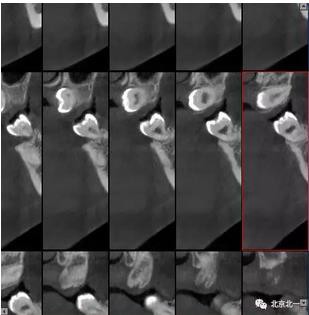

圖四:冠狀面截圖牙根位于唇側(cè),牙冠位于腭側(cè)。

圖五:矢狀位截圖可見牙冠截面。